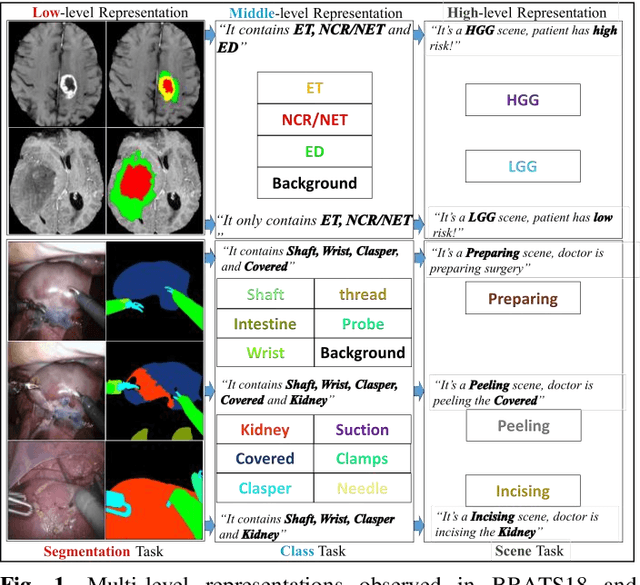

Abstract:Semantic segmentation is essentially important to biomedical image analysis. Many recent works mainly focus on integrating the Fully Convolutional Network (FCN) architecture with sophisticated convolution implementation and deep supervision. In this paper, we propose to decompose the single segmentation task into three subsequent sub-tasks, including (1) pixel-wise image segmentation, (2) prediction of the class labels of the objects within the image, and (3) classification of the scene the image belonging to. While these three sub-tasks are trained to optimize their individual loss functions of different perceptual levels, we propose to let them interact by the task-task context ensemble. Moreover, we propose a novel sync-regularization to penalize the deviation between the outputs of the pixel-wise segmentation and the class prediction tasks. These effective regularizations help FCN utilize context information comprehensively and attain accurate semantic segmentation, even though the number of the images for training may be limited in many biomedical applications. We have successfully applied our framework to three diverse 2D/3D medical image datasets, including Robotic Scene Segmentation Challenge 18 (ROBOT18), Brain Tumor Segmentation Challenge 18 (BRATS18), and Retinal Fundus Glaucoma Challenge (REFUGE18). We have achieved top-tier performance in all three challenges.